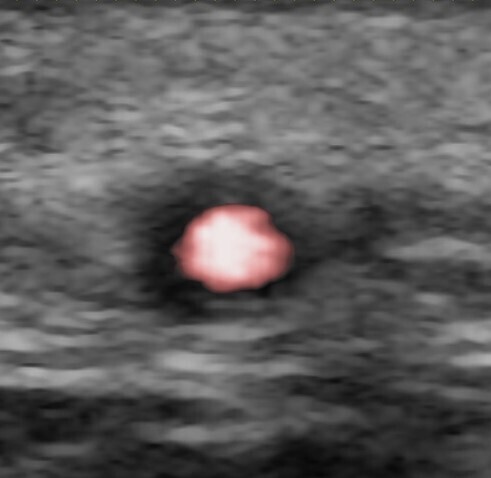

L'écho-Doppler a une place dans le diagnostic de la maladie de HORTON, mais attention, il ne faut pas se focaliser sur l'artère temporale. On peut détecter le signe du halo au niveau : de la maxillaire interne, de l'artère sous-clavière, de l'artère axillaire, exceptionnellement au niveau de l'aorte abdominale.